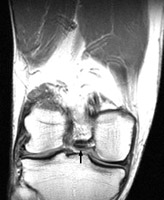

Diagnosis:Bucket-handle tear of the menisci Discussion:The displaced fragment of a bucket handle tear of the meniscus can move medially to lie within the intercondylar notch. The fragment-in-notch sign is defined as a band like area of low signal intensity within the intercondylar notch, not appearing on the same slice as the PCL. The sign, when identified, can be valuable in picking up a bucket handle tear of the meniscus. References: